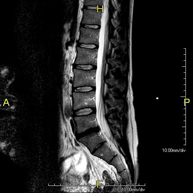

Prueba diagnóstica no invasiva que consiste en la obtención de imágenes de alta definición anatómica de la columna dorsal mediante el empleo de un campo electromagnético y ondas de radio (con un emisor y un receptor). No utiliza radiación ionizante. Indicaciones: traumatismo, problemas degenerativos, hernias, tumores. - RM Columna Lumbar

Prueba diagnóstica no invasiva que consiste en la obtención de imágenes de alta definición anatómica de la lumbar y sacra mediante el empleo de un campo electromagnético y ondas de radio (con un emisor y un receptor). No utiliza radiación ionizante. Indicaciones: traumatismos, ciática, hernias discales, tumores, infecciones. - RM Sacro-cóccix

Prueba diagnóstica no invasiva que consiste en la obtención de imágenes de alta definición anatómica de la columna dorsal y lumbar mediante el empleo de un campo electromagnético y ondas de radio (con un emisor y un receptor). No utiliza radiación ionizante. Indicaciones: traumatismo, degeneración de la columna, hernias.